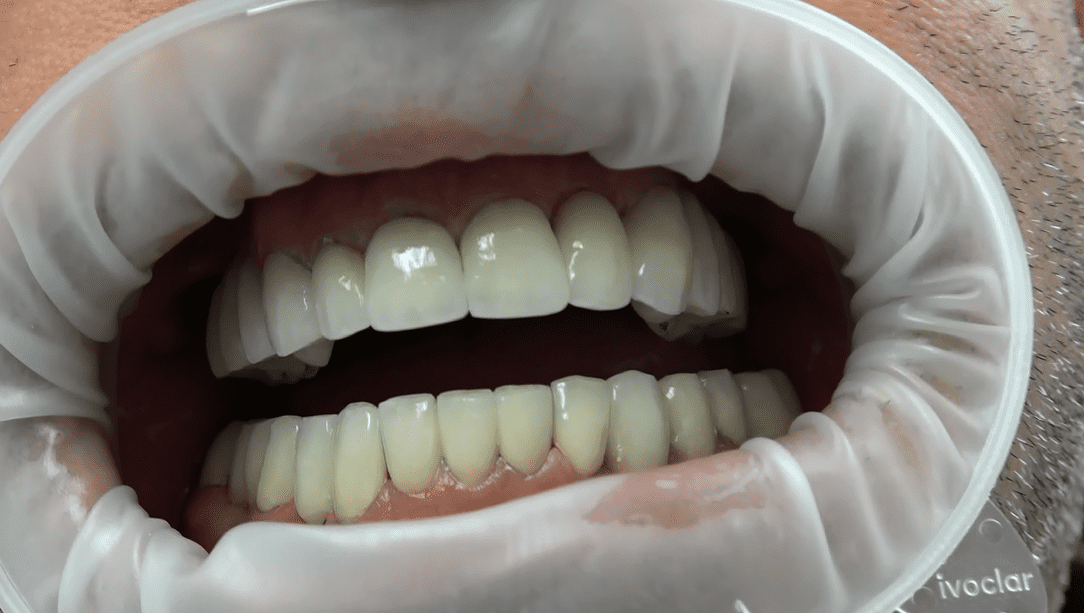

Ulteriore caso clinico

Le nostre protesi circolari senza gengiva sono un capolavoro artigianale, realizzato su misura per ogni paziente. La forma circolare della protesi è studiata per adattarsi armoniosamente alla tua bocca, distribuendo uniformemente la pressione masticatoria e garantendo comfort e stabilità.

• La nostra firma è la protesi circolare senza falsa gengiva. Eliminiamo i confini artificiali per un sorriso che sembra naturale e autentico.